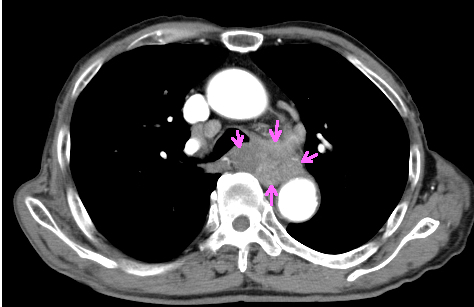

手術の可能性、転移の有無を調べるため造影CTを施行

造影CT検査で食道壁から周囲の縦隔内に浸潤を認める

造影CT